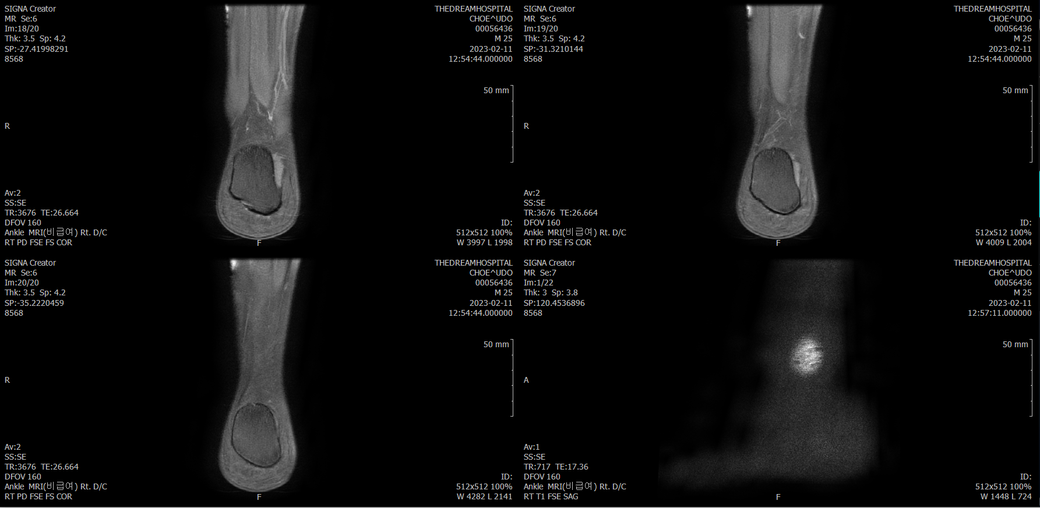

오른발목 mri 전체사진입니다. 제가 병원을 갈수없는상황인지라.... 봐주시면 감사하겠습니다.

엑스레이에서는 문제가 없다고 하여 오른발목 mri촬영했습니다.